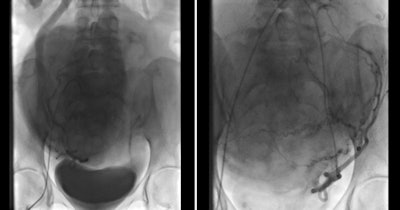

لقد أثارت قسطرة شرايين الرحم اهتمامًا عالميًا كبيرًا منذ أن تم استخدامها لأول مرة لمعالجة أعراض أورام الرحم الليفية في فرنسا في عام1995 . إن مبدأ قسطرة شرايين الرحم هو عبارة عن وقف تزويد أورام الرحم الليفية بالدم والغذاء مما يؤدي إلى ضمورها وانكماشها تدريجياً . ويتم تحقيق ذلك عن طريق حقن جزيئات مجهرية في شرايين الرحم من خلال القسطرة دون تدخل جراحي.

الجزيئات المجهرية المستخدمة في قسطرة الأورام الليفية الرحمية في مستشفى العين في مايو 2014تم توفير جميع الصور من قبل الدكتور جمال القطيش.